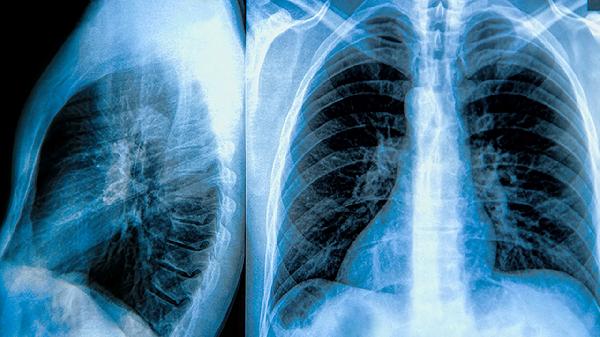

1、影像学检查是诊断肺大泡的首要方法。胸部X线可以初步发现肺大泡的存在,表现为肺部透亮区域,但分辨率有限。CT扫描尤其是高分辨率CT,能够更清晰地显示肺大泡的大小、位置和数量,帮助鉴别肺大泡与其他肺部疾病如肺气肿、肺囊肿等。